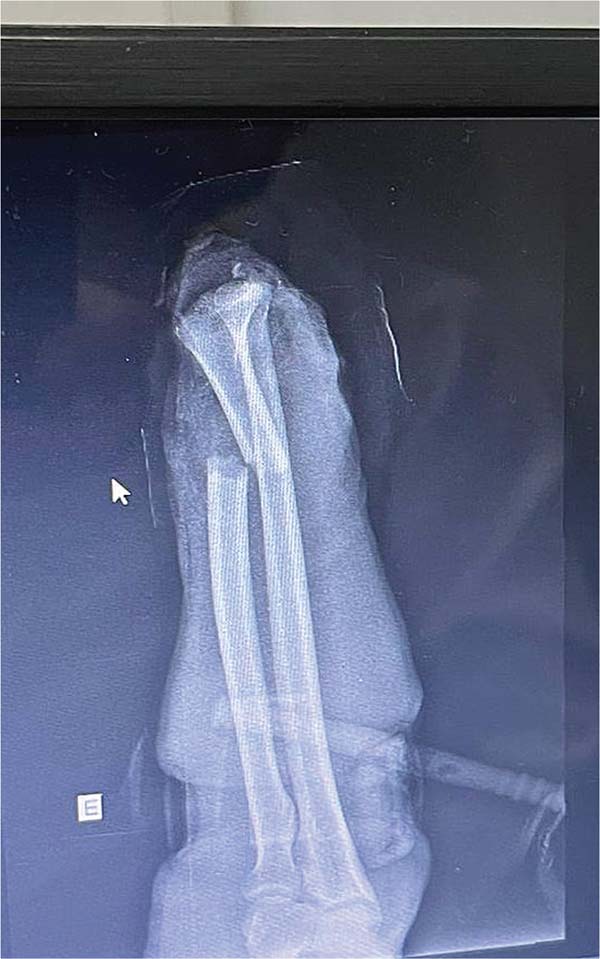

Um paciente (IPB) de 56 anos, do sexo masculino, casado, natural e procedente de Fortaleza, deu entrada no hospital decorrente de acidente por serra em ambiente de açougue. Ele apresentava amputação total da mão esquerda ao nível de punho com exposição óssea e tendínea, com torniquete no esquerdo e mão acondicionada em recipiente com gelo. Relatou que o acidente ocorreu há aproximadamente 40 minutos. Ao exame apresentava-se estável, porém moderadamente hipocorado devido a perda sanguínea significativa, porém sem perda de consciência com frequência cardíaca próximo a 110 bpm se enquadrando em choque hipovolêmico grau 2. Não havia sinais de escoriações ou trauma em outros membros (►Figs. 1-3).

Após medidas iniciais de acordo com o protocolo Advanced Trauma Life Support (ATLS), foram realizados os seguintes tempos cirúrgicos: dissecção de cotos vasculares com identificação de artéria radial e ulnar, e nervo ulnar e mediano; heparinização dos vasos sanguíneos da extremidade amputada; fixação óssea do rádio e bloqueio do punho com fios de Kirschner; anastomoses microvasculares primárias da artéria radial e ulnar, assim como 3 veias dorsais; sutura de nervos mediano e ulnar com uso de microscópio; finalizando com tenorrafia em bloco dos flexores e enxertia de pele sobre ferimento devido a perda de substância (►Figs. 4-7).4